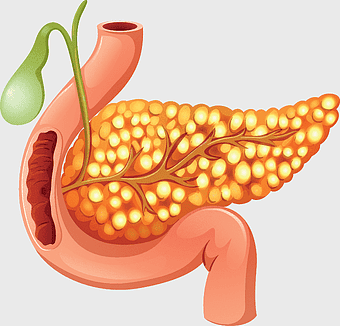

pancreas anatomy, organ illustration, digestive system, pancreatic function, endocrine gland, medical diagram, gastrointestinal health, png -